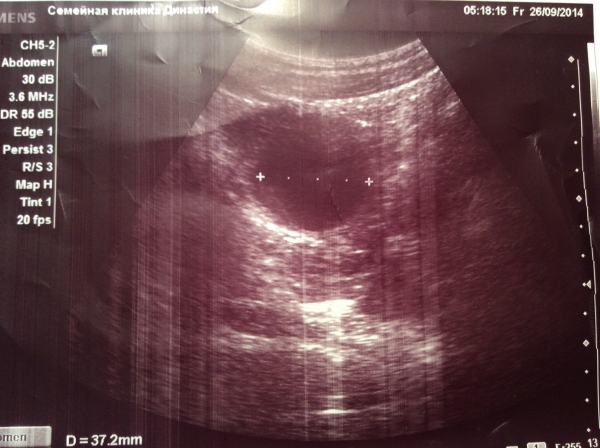

Диагноз поставлен женщине гинекологом , на УЗИ была неподготовленная , с пустым мочевым пузырем , придет повторно через неделю . Предварительно ( трансабдоминально ) рядом с маткой жидкостное образование 37 мм диаметром , с гомогенным содержимым . Похоже на кисту яичника . Ищу литературу по этой теме. ( за качество снимков извиняюсь)